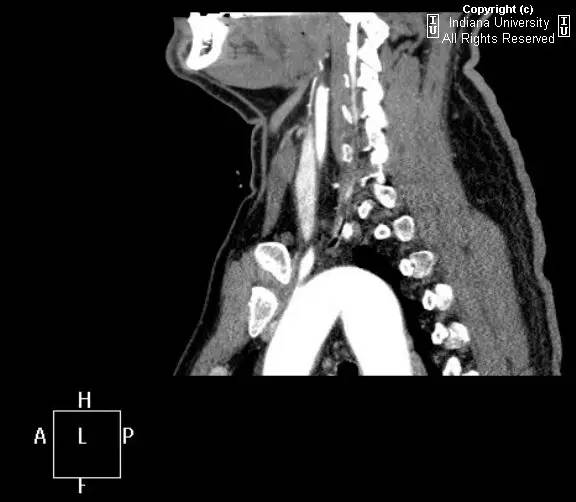

【影像学表现】胸部平片示右位主动脉弓,肺动脉突出,双肺清晰。CT示右位主动脉弓,并右位降主动脉,迷走左锁骨下动脉起自后方,从食管后走形形成血管环。迷走左锁骨下动脉与憩室相关(Kommerell)。食管因左锁骨下动脉及憩室而向前移位。

【诊断】右位主动脉弓并血管环形成、迷走左锁骨下动脉并Kommerell憩室

Right-sided aorticarch, with vascular ring and aberrant left subclavian with Kommerell\’sdiverticulum